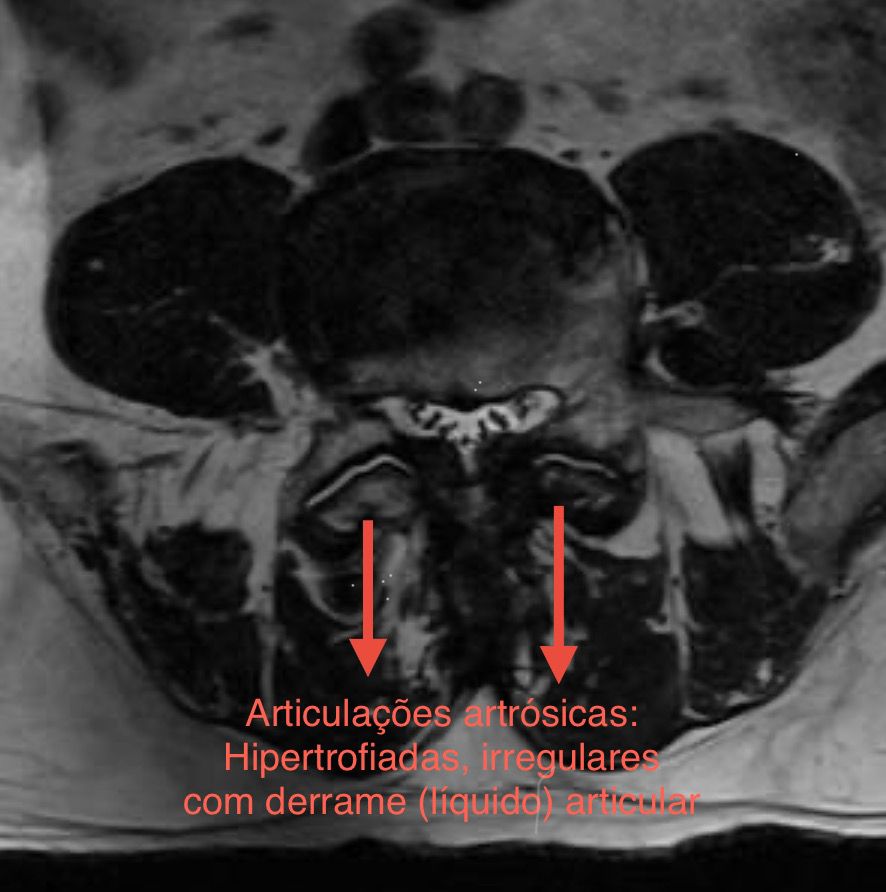

Na imagem, é possível ver as alterações a articulação da coluna em um paciente com artrose.

Quando saudável, articulação da coluna apresenta contorno regular e espaço para a passagem dos nervos.